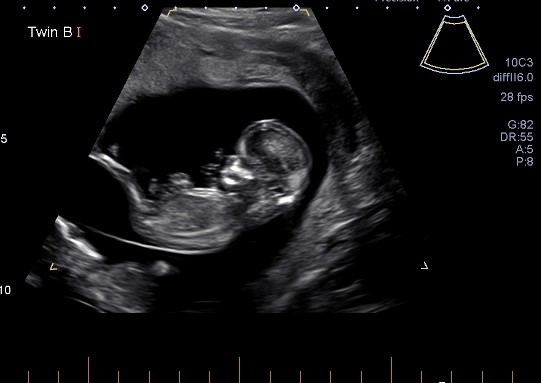

Hello, would anyone be keen to guess the genders of these 2? No good pics of baby B but baby A seems to have a clear nub. Thanks so much!

I submitted these to Nub Techs and Nubologists and both said girl but I'm a little worried there's a slight rise in the nub of Baby A, though it looks a lot different to my son's nub at this stage which had stacking. I have 3 boys so twin girls would be absolutely incredible... but we will see! I'll be sure to update x

Like I said, it's early still, but I will be extremely surprised if these darling babes are boys. Don't paint the nursery, don't shop, but Baby A in particularly looks very girly to me. I have seen a few occasions where nubs did rise even as late as the end of the 13th week but I would be feeling good about this right now.

Today I had an early gender scan (14+4) and apparently they are still looking girly! I do think Baby B's potty shot looks like a willy haha but apparently the lady has a very high success rate. She checked via nub and potty!